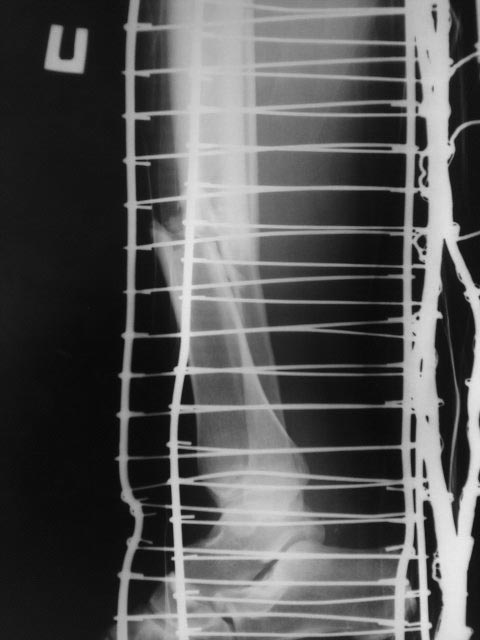

Здравствуйте! Спасибо за предоставленные снимки! Если судить по снимкам, то перелом сросся (костная мозоль со всех сторон). Необходима трансформация (уплотнение) костной мозоли, а для этого нужны нагрузка и время. Удаление пластины освободит наружный кортикал и распределит нагрузку равномерно по всей окружности кости. Что касается аутопластики, то она не показана при гипертрофическом псевдоартрозе. Ещё раз спасибо!

По данным рентгенограммам - перелом сростается. Исключить сомнения - сделать МСКТ. Если на МСКТ - данных за ложный сустав нет, то удалить металлоконструкцию и пользоваться ортезом на голень до достижения более прочной костной мозоли по данным контрольных R-грамм.

Еще бы понятно околосуставной, но зачем диафизарный перелом tibia в наши дни синтезировать пластиной?

Периостальная спайка вроде там все-таки есть. Наверно, ничего не надо делать. Или далить ближайшие к перелому винты, чтобы не было концентрации напряжений.

Спасибо за все комментарии, пока ждем результатов от УВТ и контрольный рентген через 2 месяца - вижидательная тактика более правильна (как по мне) в данном случае

Выложу цифровые рентгены, потом обсудим повторно